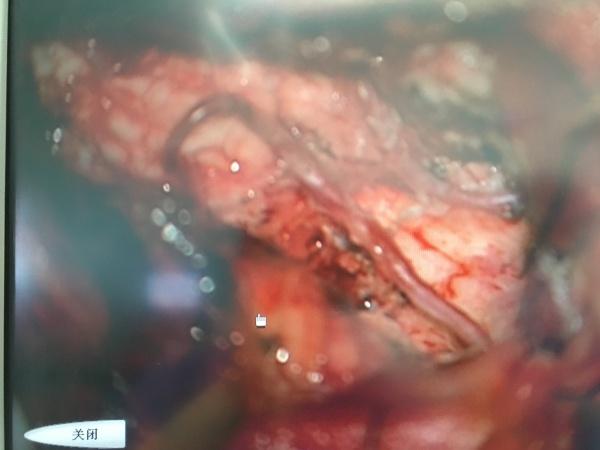

手术顺利,术后CT如上图所示,患者有谵妄症状,已予以对症处理,现患者有轻微水平眼震,较前明显好转. 手术很大,很成功,并不只是神经外科一家之功,麻醉师的强力支持绝对是重中之重!尤其是关乎脑干的手术!